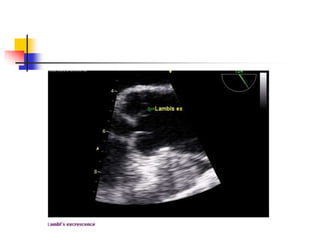

Aortic Valve Mass: Lambl's

Excrescences

 Fine filamentous strands, Lambl excrescences, can

be seen originating from the aortic valve of elderly

patients.

 It is considered as a degenerative change on the

surface of leaflets due to mechanical wear and tear.

 Multiple adjacent excrescences may stick together

and grow up to large, complex form called "giant

Lambl's excrescence". Whether the excrescences

may serve as a nidus for bacterial growth or cause a

systemic embolism is controversial.

 In echo, it appears as very thin, delicate, lint-like mobile

threads arising from the free borders or ventricular

surfaces of aortic leaflets . Improving image quality

increases to find this lesion.

 significance of Lambl's excrescences lies in the

differential diagnosis from the vegetation of infective

endocarditis.

 It is challenging in most cases, and a diagnostic decision

making often depends on clinical settings.